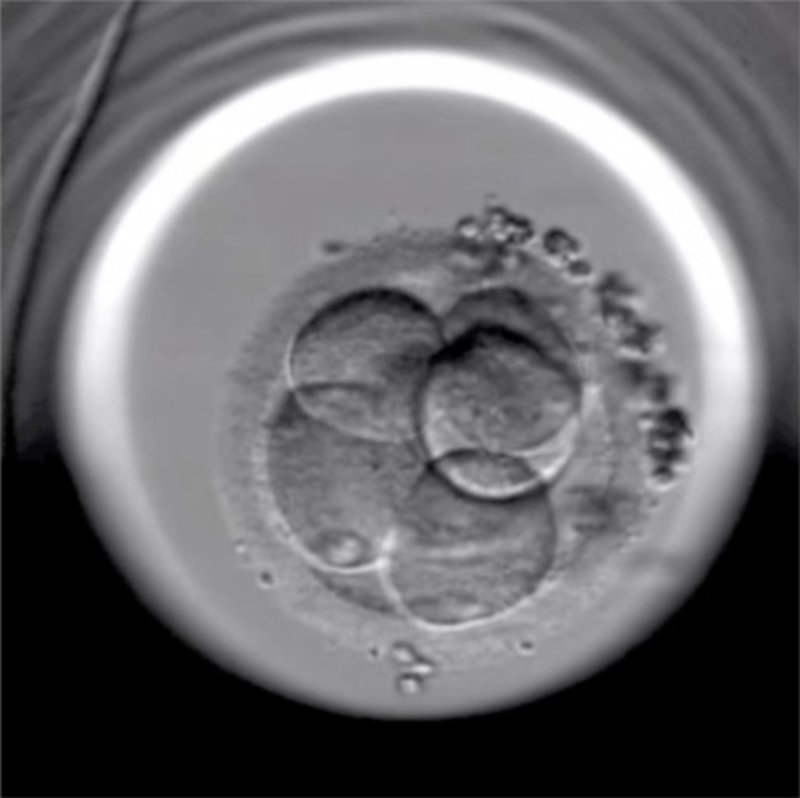

Embrión Fertilizado. Reproducción In Vitro

Foto: INSTITUT MARQUÈS DE BARCELONA